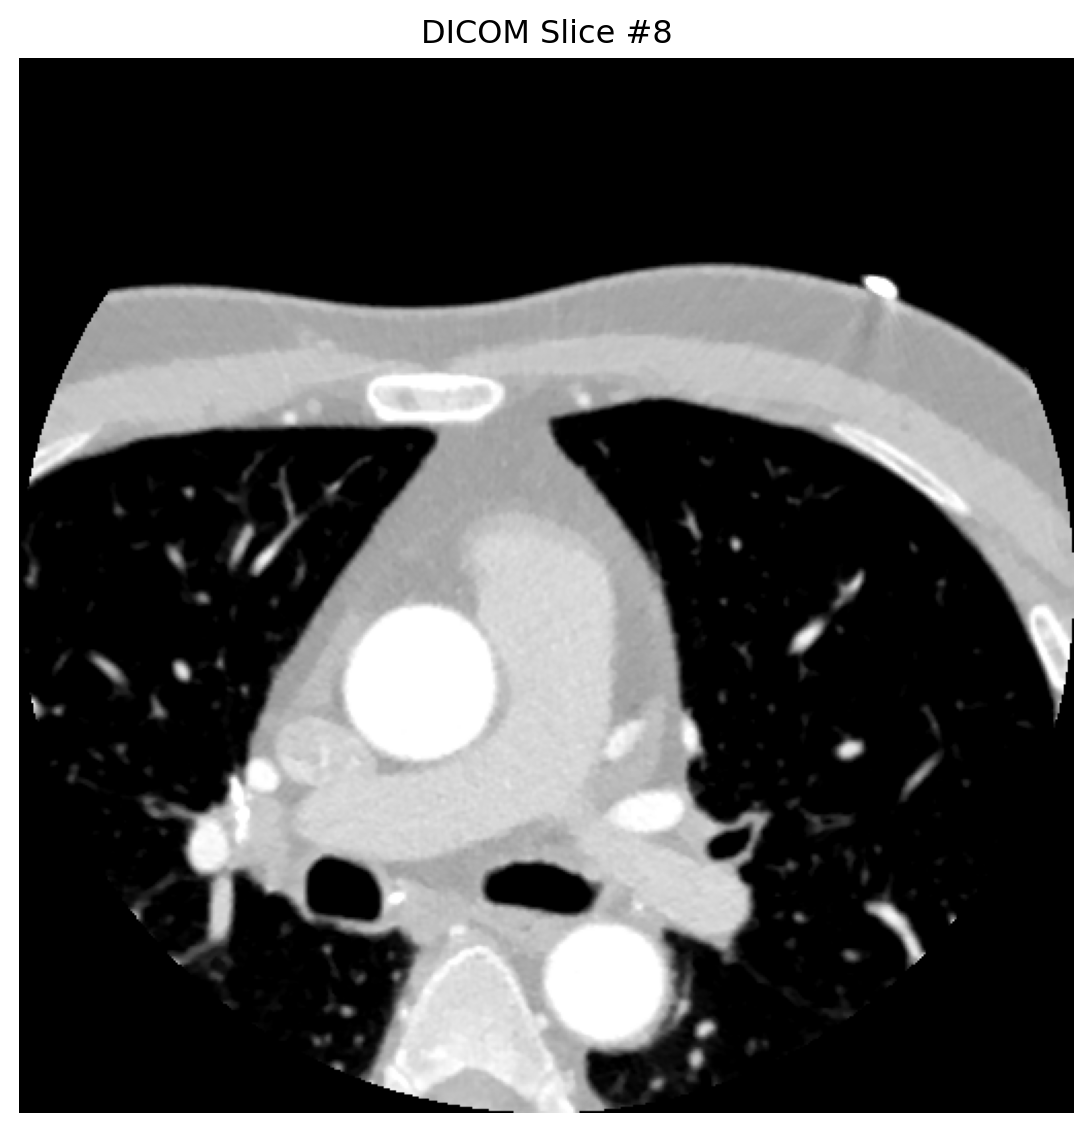

# 分析多个代表性切片

for slice_idx in [0, 4, 8]:

dataset = analyze_dicom_slice(slice_idx)